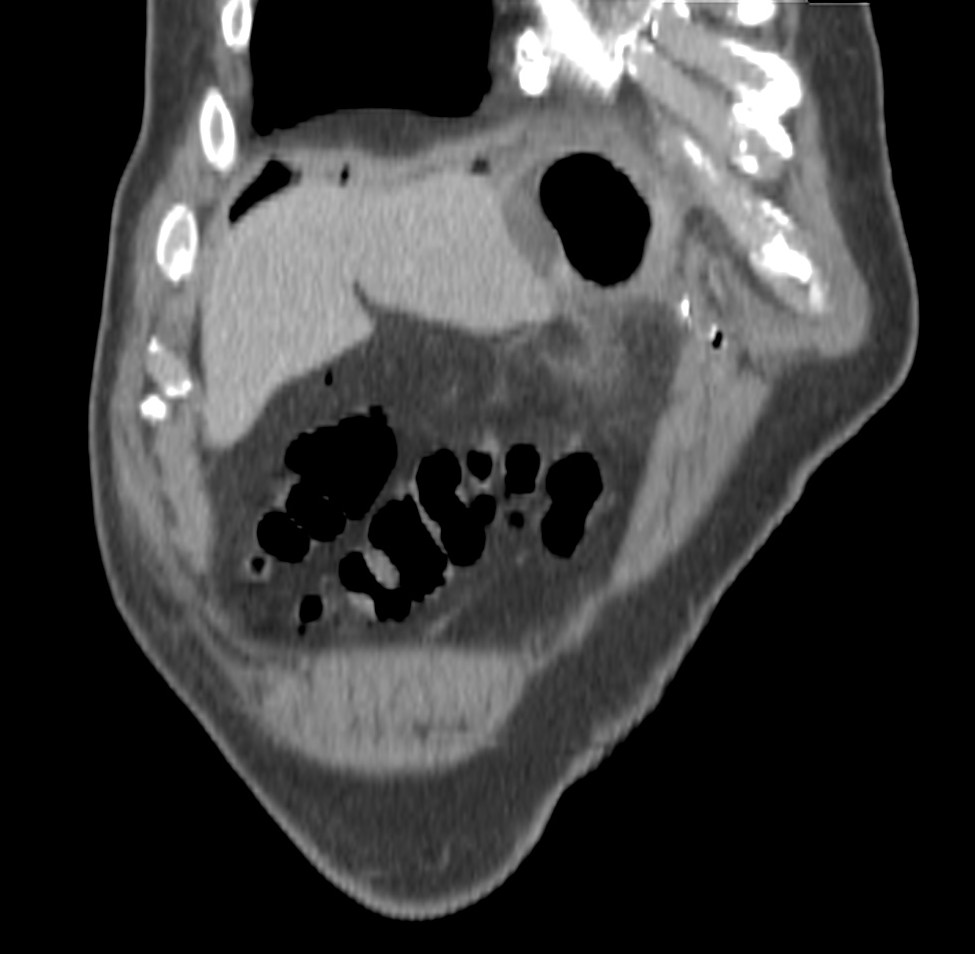

CASO: cáncer de mama. Control anual.

Hallazgos:

- Se observa un aumento de densidad con agrupación broncovascular que produce un borramiento del borde cardicaco derecho; hallazogos compatibles con atelectasia en el lóbulo medio. Véase el TC a continuación: